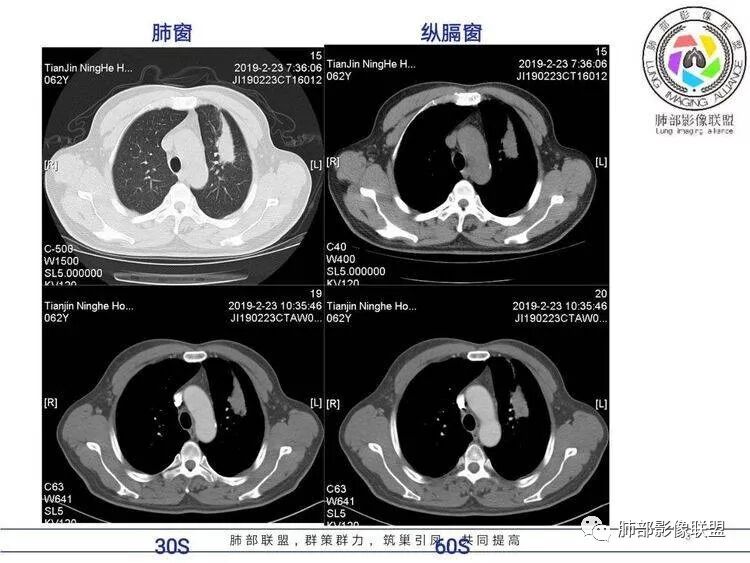

病例资料

王秀仙:左肺上叶肿块,边缘平直收缩,周围可见长索条,轻度强化,密度不均可见低密度坏死,考虑结核。鉴别腺癌。Yiren  Sishui(厶水伊人):晨读:左肺上叶肿块,近胸膜侧光滑,提示符合淋巴回流病变,周围条索,符合肉芽肿性病变,环形强化,中心坏死,考虑结核可能luys:左肺上叶病变,沿支气管分布,边缘平直收缩,周围见长索条,轻度强化,伴边界可见低密度坏死灶。考虑特殊感染。灶内支气管中断,临床以咯血就诊,鉴别肿瘤。博麟:左上胸廓稍缩小,长条索病灶,冠状位似见支气管截断,坏死边界似乎欠清,猜个纤维条索基础上合并瘢痕癌红日东升:晨读:左上叶结块,前缘有粗大索条向前延伸,邻近前联合线明显左移,提示收缩明显。结块边缘平直、收缩;增强结块及索条明显强化,内血管走行自然,坏死灶周围似见三层结构;考虑炎性病变。wonderful:肿块实性边缘光滑  考虑良性病变 合并咯血 。结核或曲霉玫:左肺上叶不规则形软组织密度肿块影,边界清晰,期内密度不均匀,可见坏死,病灶向前呈条索状延伸,矢状位病灶形态欠规整,似有血管中断,考虑恶性病变可能,待除外结核?张帅:左肺上叶病变,病变周围平直,长毛刺,病灶内可见低密度区及支气管征,矢状位提示前段阻塞,病灶内气管不规则扩张,病灶周围有卫星灶,考虑良性病变:结核?我心飞翔:病灶边缘平直,中央可见坏死,周围磨玻璃边界欠清,考虑炎性病变张延军:左肺上叶尖后段肿块,边缘以平直为主,局部膨隆,内见片状坏死区,边界欠清,相应尖后段支气管闭塞,考虑占位并不张,腺癌?建议抗炎治疗后复查丽:左肺上叶病变,边缘平直,并可见长索条,增强后密度不均,可见坏死,首先考虑结核,但重建后支气管走形欠连续,似有截断,恶性待排毛勤香:左肺上叶病灶,边缘平直为主,周围索片影,增强强化不均匀,内有坏死,重建支气管走行欠规则,似有截断,老年男性,需排除恶性(鳞癌?)并阻塞性肺炎可能王萍:左肺上叶团片,大部分边缘平直、凹陷,周围见少许条片模糊影,增强内见坏死区,余区域较均质,其内支气管部分通畅,部分变窄。咯血病史,无发热,考虑肉芽肿性炎可能性大,结核或放线菌等,肿瘤待排THINKER:左上叶,占位,围绕尖后段支气管,U型凹丶平直,长索条,有轻强化及低密度,考虑良性的,首选OP,老年不发热丶咯血,鉴鳞癌、TB飞鹰行动:左肺病灶,有明显的收缩表现,增强后病灶内部可见低密度无强化区,病灶内支气管轻度扩张呈串珠状改变,支持炎性病变,结核可能性大。杨泽锋:支持炎性病变伴小脓腔形成,但不支持结核,因为病灶内可以可见血管影THINKER:问一下各位老师:这个给的强化,是肺动末期丶主动脉未期`延迟期?大雄:老年男性,左肺上叶前段条片状实变影伴周围长条索,境界清晰,边缘部分锐利光滑、部分毛糙,增强可见中央局部坏死,周围无强化区轻中度均匀强化,无钙化,无明显卫星灶,无胸膜明显牵拉凹陷。病灶整体收缩力有,张力不明显,肿瘤概率小。临床无明显急性感染症状,倾向于慢性增生性炎症,累及段支气管,引起了咯血。结核多见,但慢性结核肉芽肿一般强化没这么明显。OP不除外。老年男性如果有长期吸烟史,鳞癌不能完全排除,鳞癌的坏死强化都符合,鳞癌收缩力也不强,形态更是变化无常左手:老年男性,咯血,左肺上叶长条样结节,边缘见牵拉影,支气管堵塞,病灶内见坏死,坏死边缘偏清,考虑鳞癌,鉴别结核宇宙星空:支持恶性。鳞癌可能性大。支气管截断及空泡征

Shelia:考虑机化性肺炎伴小脓肿形成?炎性肌纤维母细胞瘤?鉴别癌食客:左肺上叶病灶,边缘平直,周围条片影,增强内见坏死区,内支气管部分通畅,咯血病史,无发热,考虑结核,肿瘤不除外。管洪林:左肺上叶尖后段病变,整体边缘平直,部分稍收缩,临近长索条影,胸膜缘可见轻度牵拉,增强后整体强化明显,其内可见低密度类圆形坏死区,边界清,首先考虑op并小脓肿形成,但部分层面显示小支气管受阻,是否层面原因?管洪林:若是支气管阻塞,鳞癌作为鉴别雪上一枝蒿(陈显静):他这个动脉期是不是不是很明显啊,觉得跟静脉期差不多,强化值也不好分辨?徐超:左肺上叶实变,边缘平直,周围无磨玻璃及卫星灶,病灶内坏死,强化后边界清楚,无壁结节,余病灶轻中度均匀强化(对比肌肉),增强后血管显影清楚自然,未见破坏边缘毛糙,血管旁条形无强化区(粘液?)整体符合炎性特点,炎性假瘤或op可能,伴小脓肿;结核放后面待排(结核病灶内血管完好,边缘清楚,且强化近中度,不是很合理,肉芽肿到也可以)。红日东升:平扫和强化窗宽窗位不一样良孑:左上实变,有平直及长毛刺,其内支气管牵拉性扩张,提示收缩力较强,无卫星灶,强化不支持TB,均匀强化,无分叶不支持鳞癌,影像上提示慢性进程,考虑OP并脓肿,鉴别炎肌母。

1.外观呈三角形,尤其是锐三角形的病灶,一般是最不支持肿瘤的。

2.小病灶影像上观察到液化坏死一般不支持肿瘤。

3.腔内壁太规则一般不支持肿瘤。

4.炎性分泌物可以形成一定程度堵塞,但很少截断支气管。

5.结核可以强化不显著,但病灶不靠边,没有卫星灶,似乎支持点不多。